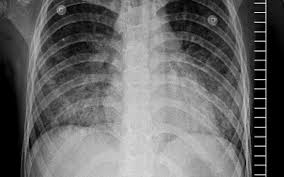

Acute Respiratory Distress Syndrome Wet Lung

Acute Respiratory Distress Syndrome Wet Lung from cdn-prod.medicalnewstoday.com

Ards, or acute respiratory distress syndrome, is a lung condition that leads to low oxygen levels in the blood. Covid‐19 ards is a predictable serious complication of covid‐19 that requires early recognition and comprehensive management this disease is still too strange to us, and there are too many doubts, says dr ling qin (lq), after reviewing more than 400 patients with coronavirus disease 2019 (covid‐19) pneumonia in wuhan union hospital, china. In ards, fluid builds up inside the tiny air sacs of the lungs, and surfactant breaks down. Acute respiratory distress syndrome (ards) is a form of acute lung injury and occurs as a result of a severe pulmonary injury that causes alveolar damage heterogeneously throughout the lung. Most people who get ards are already at the hospital for trauma or illness. Causes may include sepsis, pancreatitis, trauma, pneumonia, and aspiration. Ards is a type of acute respiratory failure caused by fluid buildup in your lungs. Acute respiratory distress syndrome (ards) is a medical condition in which the lungs are not working properly and oxygen blood levels are too low.

This month marks the 50th anniversary of the first description of the condition now termed the acute respiratory distress syndrome, or ards. Breathing becomes difficult and oxygen cannot get into the body. In ards, fluid builds up inside the tiny air sacs of the lungs, and surfactant breaks down. Acute respiratory distress syndrome (ards) is a condition that causes fluid to build up in your lungs so oxygen can't get to your organs. Acute respiratory distress syndrome (ards) is a form of acute lung injury and occurs as a result of a severe pulmonary injury that causes alveolar damage heterogeneously throughout the lung. The condition leads to a buildup of fluid in the air sacs which prevents enough oxygen from passing into the bloodstream. The authors of this review discuss our current understan. Ards is a medical emergency. Acute respiratory distress syndrome (ards) is a serious lung condition that causes low blood oxygen. Too much fluid in your lungs can lower the amount of oxygen or. For those who survive, a decreased quality of life is common. Ards progresses through several phases after a direct pulmonary or indirect extrapulmonary insult. The diagnosis of ards is based on fulfilling three criteria: